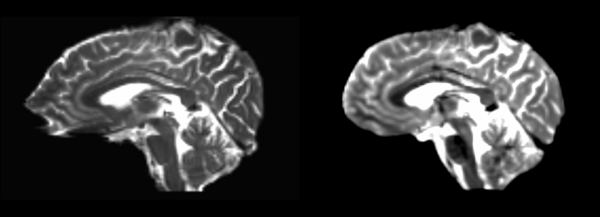

T2 to DTI baseline registration

Slicer modules

At first, I attempted to do whole volume registration, but it quickly became clear that masked volumes would be needed to perform even semi-accurate registrations. A few examples of non-masked registrations will be left, but all other transforms will be done with skull-striped masked volumes.

B-Spline

- DTI-baseline -> 53-t2 = Bspline3

Fits the cortex on the baseline to the skull on the t2. Retry with a skull stripped t2.

Diffeomorphic Demons

- DTI-baseline -> 53-t2 = Demons3

Rigid

Brain tilted to appropriate angle, but DTI strecthing clear in frontal and parietal lobes. Cerebellum okay, middle quarter of rest of brain roughly matches.